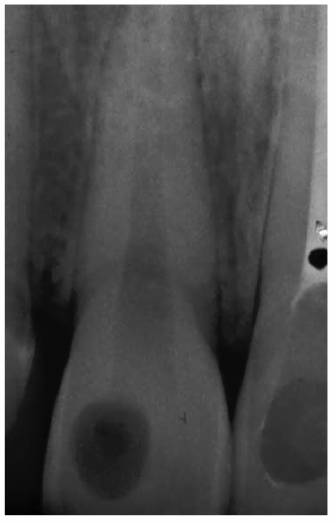

Transillumination via a fiber-optic light may be of great assistance in

detecting color shifts in a crown (Figures 19-1A, and 19-1B). A tooth with a pink or reddish

hue would more than likely indicate internal hemorrhage from a recent injury (Figure 19-2), a dental procedure (Figure 19-3), or gingival tissue hyperplasia

Figure 19-1A: Transillumination of a maxillary left central incisor with a necrotic pulp.

Figure 19-1B: Transillumination of the adjacent tooth with a vital pulp. Because there is active blood flow through the live pulp tissue, the tooth appears brighter to the fiber-optic light than the adjacent tooth with a necrotic pulp.

Figure 19-4A: Pink spot as a result of external resorption.

Figure 19-4B: Radiograph of the same tooth showing external resorption.

Figure 19-4C: Pink spot as a result of internal resorption.

Figure 19-4D: Radiograph of the same tooth showing internal resorption.